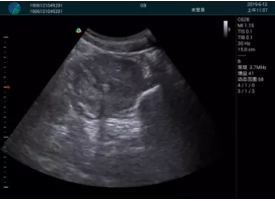

抽吸結(jié)束后縱切子宮,孕囊已被完全抽吸,未見明顯殘留

橫切子宮,發(fā)現(xiàn)右側(cè)宮腔靠近宮角處有少許脫模樣殘留